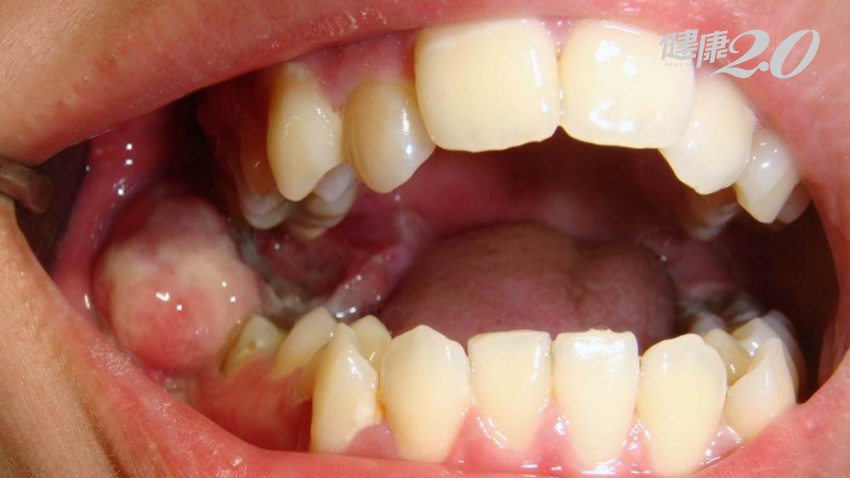

18歲的游同學下顎痛到不同,牙醫就診才發現是右下智齒無法正常生長、發炎,醫師遂為其拔掉智齒。但智齒拔完仍持續疼痛,兩個月了靠消炎止痛藥都治不好,便到台北慈濟醫院檢查,未料化驗後才發現,游同學拔智齒的發炎組織轉變成口腔癌,癌細胞擴散到整個下顎骨!

才18歲,沒吸菸也沒嚼檳榔,為什麼只是智齒長不好就得口腔癌?游同學的主治醫師,台北慈濟醫院牙科部顎面外科主任夏毅然表示,智齒生長在口腔最後方,又是最晚生成的牙齒,很容易因生長空間不足向前傾斜、無法正常萌發。

這些長歪的智齒沒有咀嚼等功能,而且又因位置和角度不容易清乾淨,造成蛀牙、牙齦發炎、牙周病、蜂窩性組織炎等問題的機率很高,連帶危害周邊牙齒的健康機率高達81%以上。即使智齒沒長歪,但沒對應咬合的牙齒,則可能會過度萌發影響咬合,或是反覆刮傷周圍的口腔黏膜,長期下來很容易癌變。所以常會聽到牙醫師建議民眾把智齒拔掉,就是這個原因。

而有些完全深埋在骨頭裡的智齒,雖然沒有蛀牙或發炎的風險,可以暫不拔除,但也要小心有3%的機率可能會形成囊腫,也有少部份發展成口腔癌。